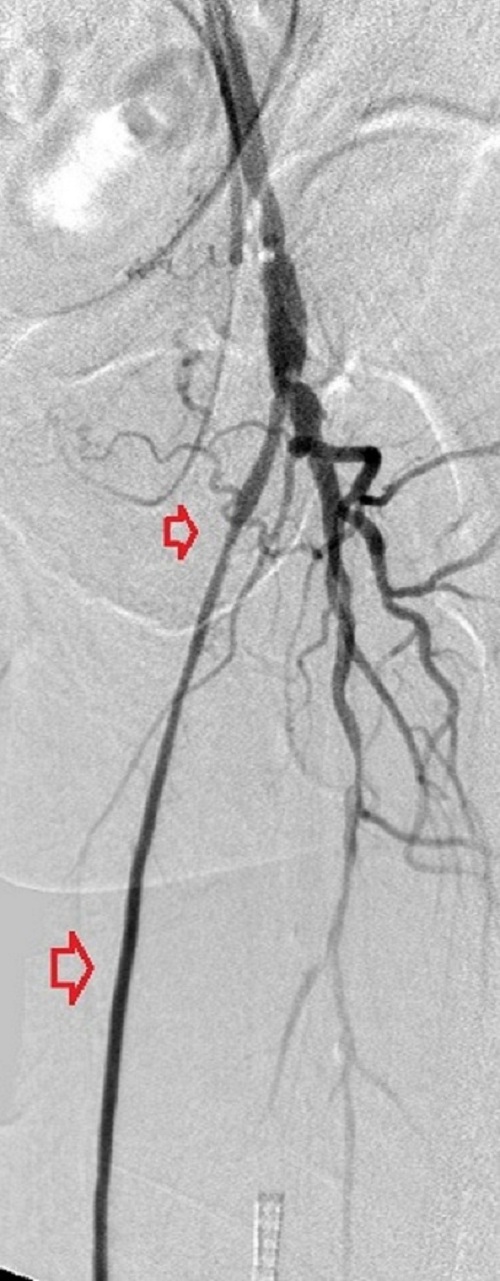

Key to images:

Bottom panel: Post intervention run-off arteriogram of the left lower extremity showing, from left to right, the proximal and distal segments of the re-opened left femoro-popliteal bypass (red arrows on images 1, 2, and 3). Contrast the full-column opacification of the below-knee left popliteal artery, arrowed blue on the 3rd image, and the enhanced visibility of the three-vessel subpopliteal domain to their vestigial appearances on the pre-intervention images, when they were poorly fed through collaterals.

When blood flow into or out of a bypass fails, it thromboses and its salvage includes gaining access into it and removing the clot in addition to determining the reason for its failure. Such clot removal may be mechanical, as is frequently the case in acute graft failure, or through thrombolysis, as is the case in later failures. The above images illustrate the later scenario in which the patient presented about 1 year after a left femoropopliteal bypass was fashioned for them. I crossed into the lumen of the bypass conduit from a right common femoral arterial puncture and advanced an infusion cather into it for overnight continuous alteplace infusion following a bolus dose. (I favor 5 to 10 mg of alteplace bolus, followed by continuos infusion at 0.5 mg per hour, in company with fixed unfractionated heparin infusion at 500 units to 600 units per hour after a bolus dose of 3000 units to 5000 units). In this case the bypass proved to be a vein conduit connecting the left common femoral artery, proximally, to the mid popliteal artery, distally, without intimal hyperplasia. The cause of the failure was diminished inflow due to left iliac disease.The final runoff images reveal a three-vessel tibial domain continuous with a near-normal plantar arch.